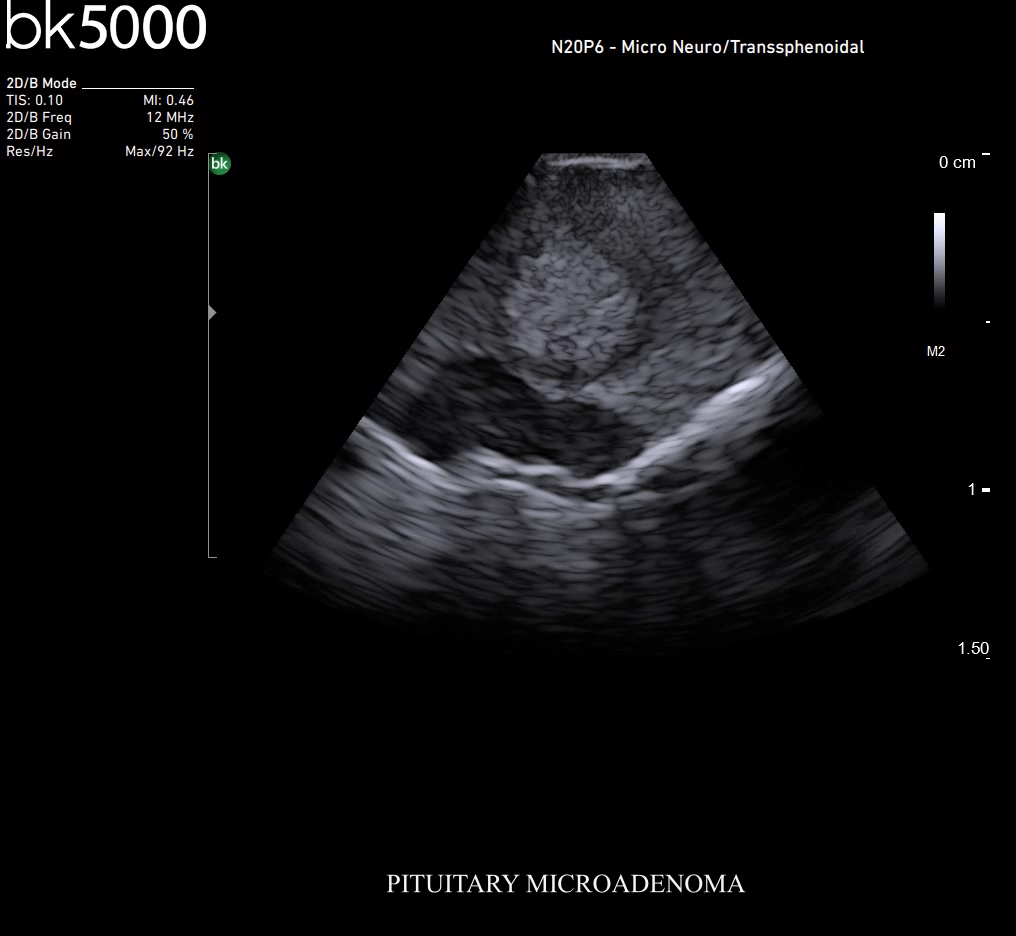

Ultrasound can improve neurosurgical procedures by helping you navigate and identify lesions and anatomical structures in real-time. This is particularly important as the data obtained from a preoperative CT or MRI scan can be outdated at the time of surgery. The bk5000 neurosurgical system provides the highest quality images that allow you to clearly see the margins of a lesion and to determine the best course of action. Using advanced graphics processing technology, this powerful system provides immediate, auto-optimized images that allow you to see the information you need, faster.

Transducers designed for Neurosurgery

The specialized, high-resolution, sterilizable neurosurgery transducers enable you to obtain detailed images of the brain and spinal cord. They have a convenient Smart™ button that lets you activate the transducer, then freeze, store or print the images at the press of a button. Disposable, easy-to-use needle guides assist with targeting lesions.